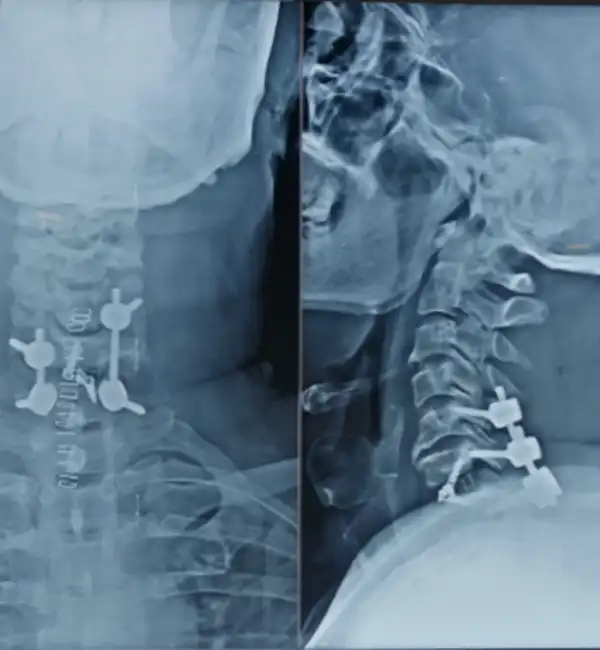

T2 Fracture Post Op

C6-7 Fracture dislocation Post op X ray